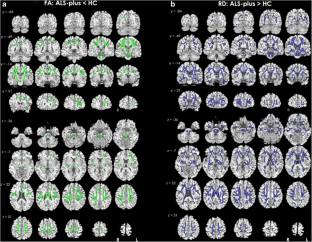

The phenotypic heterogeneity in amyotrophic lateral sclerosis (ALS) implies that patients show structural changes within but also beyond the motor cortex and corticospinal tract and furthermore outside the frontal lobes, even if frank dementia is not detected. The aim of the present study was to investigate both gray matter (GM) and white matter (WM) changes in non-demented amyotrophic lateral sclerosis (ALS) patients with or without cognitive impairment (ALS-motor and ALS-plus, respectively). Nineteen ALS-motor, 31 ALS-plus and 25 healthy controls (HC) underwent 3D–T1-weighted and 30-directional diffusion-weighted imaging on a 3 T MRI scanner. Voxel-based morphometry and tract-based spatial-statistics analysis were performed to examine GM volume (GMV) changes and WM differences in fractional anisotropy (FA), axial and radial diffusivity (AD, RD, respectively). Compared to HC, ALS-motor patients showed decreased GMV in frontal and cerebellar areas and increased GMV in right supplementary motor area, while ALS-plus patients showed diffuse GMV reduction in primary motor cortex bilaterally, frontotemporal areas, cerebellum and basal ganglia. ALS-motor patients had increased GMV in left precuneus compared to ALS-plus patients. We also found decreased FA and increased RD in the corticospinal tract bilaterally, the corpus callosum and extra-motor tracts in ALS-motor patients, and decreased FA and increased AD and RD in motor and several WM tracts in ALS-plus patients, compared to HC. Multimodal neuroimaging confirms motor and extra-motor GM and WM abnormalities in non-demented cognitively-impaired ALS patients (ALS-plus) and identifies early extra-motor brain pathology in ALS patients without cognitive impairment (ALS-motor).